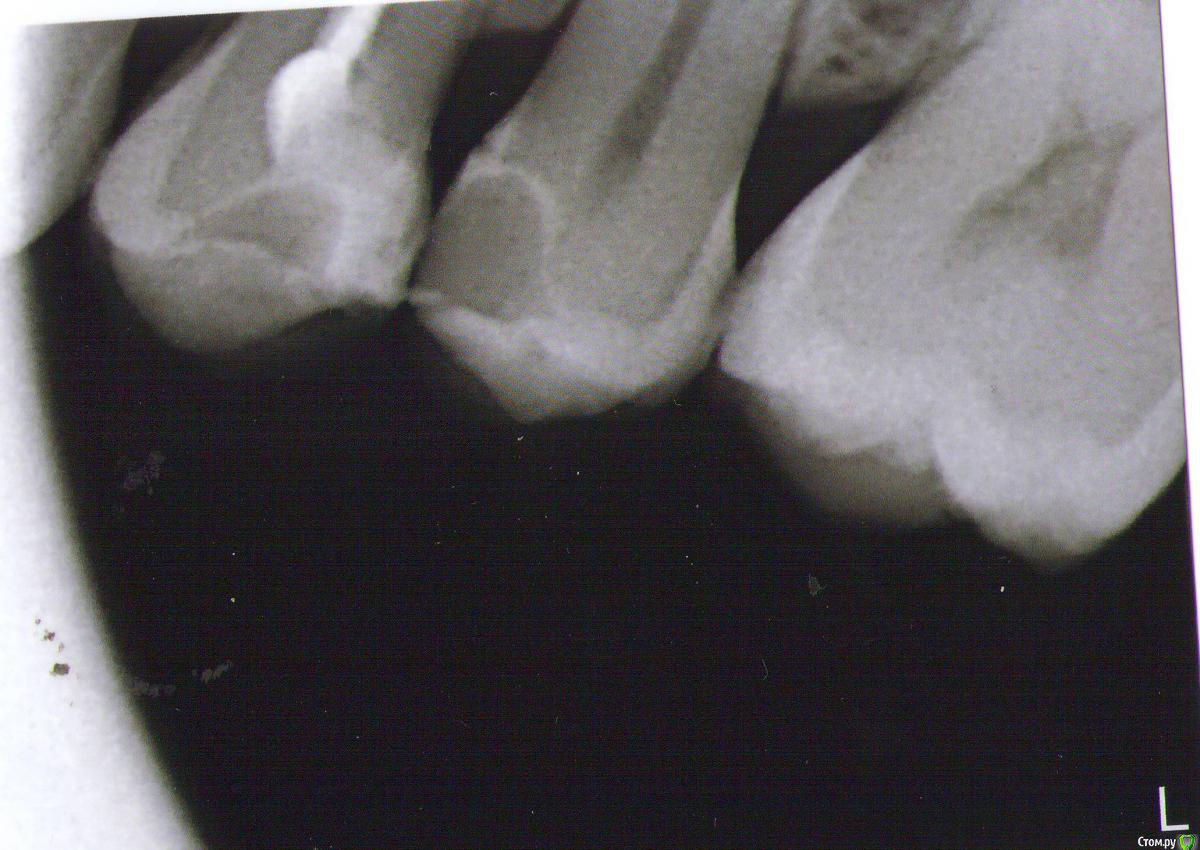

Darya87 Опубликовано 17 января, 2015 Поделиться Опубликовано 17 января, 2015 Здравствуйте. Верхний пятый зуб слева пролечен около 3 месяцев назад по глубокому кариесу. После лечения в зубе периодически возникала не сильная самопроизвольная ноющая боль и реагировал на очень холодное, типа мороженого, минут 15 не проходящей ноющей болью. Через месяц ситуация не изменилась, снова обратилась к стоматологу. Доктор сказал, что для глубокого кариеса это нормально, т.к. пролечили совсем недавно, сказал пока наблюдать. Прошло еще 1,5 месяца, ситуация не изменилась, обратилась уже к другому врачу, зубу сделали снимок и обнаружили скрытую кариозную полость на дистальной поверхности. Поставили еще одну пломбу. После второго лечения прошло уже 3 недели, зуб все также периодически ноет и реакция на очень холодное. Несколько дней бывало хорошо, уже обрадуешься и забудешь про этот зуб, а потом снова начинает ныть. Сильных ночных болей нет, при надавливании и постукивании не болит, на не слишком холодное, горячее, сладкое не реагирует. Подскажите, пожалуйста, что это может быть? Снимок перед постановкой второй пломбы. Ссылка на комментарий

Darya87 Опубликовано 17 января, 2015 Автор Поделиться Опубликовано 17 января, 2015 (изменено) Сrazyduck, спасибо. И еще скажите, пожалуйста, бывает там между 4 и 5 зубом иногда застревает зубная нить, не может ли участок ниже пломбы на 5 зубе давать такой эффект?на снимке это место обведено черным Изменено 17 января, 2015 пользователем Darya87 Ссылка на комментарий